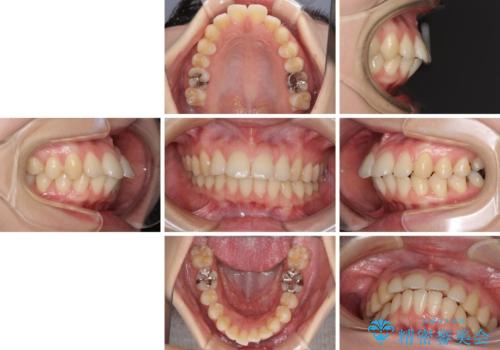

ご友人などがびっくりするほど口元の突出感を改善することができ、患者様には大変満足していただきました。